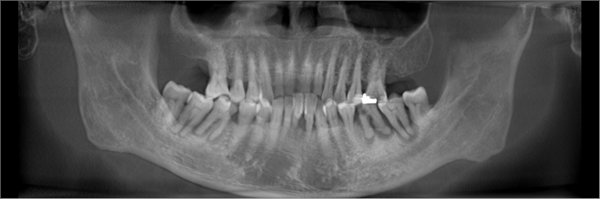

但随着年纪增大, 我牙齿逐渐松动脱落, 更糟糕的是我喜欢咬硬东西, 牙齿磨损得厉害,有一次不小心就把牙齿给咬断了。不仅痛,还刺激到牙神经很不舒服。拔了几颗牙齿之后,吃东西咀嚼都很艰难,味道也跟之前完全不同了。档期满满的,缺牙问 题 一 直 没有时间解决,让我非常困扰。牙齿缺失随之而来的是说话漏风、台词都念不准,我担心无法呈现最完美的一面给观众。

刚考虑种牙的时候,我也跟大家一样各种担忧,担心种牙痛不痛、 安不安全,等等……作为公众人物,我经常有机会访问国内的医疗机构, 在综合对比后我发现,麦芽的各项设施和技术都处于行业领先水平,设备齐全,环境干净,最重要的是他们还拥有一支由硕博专家领衔的医疗团队。

我对麦芽专家团队很有信心, 所以整个过程是全然地放松。麻药注射后我就感觉自己的嘴角慢慢失去知觉,感觉就是喝一杯咖啡的时间吧就种好了,后来我问经纪人,她说只用了8分钟!